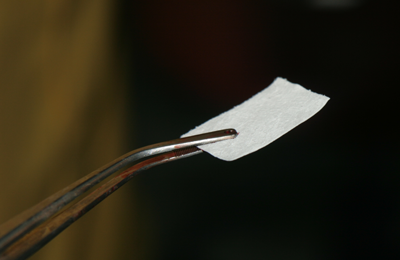

Видеоклип за открит синуслифтинг Пластинка Сasios